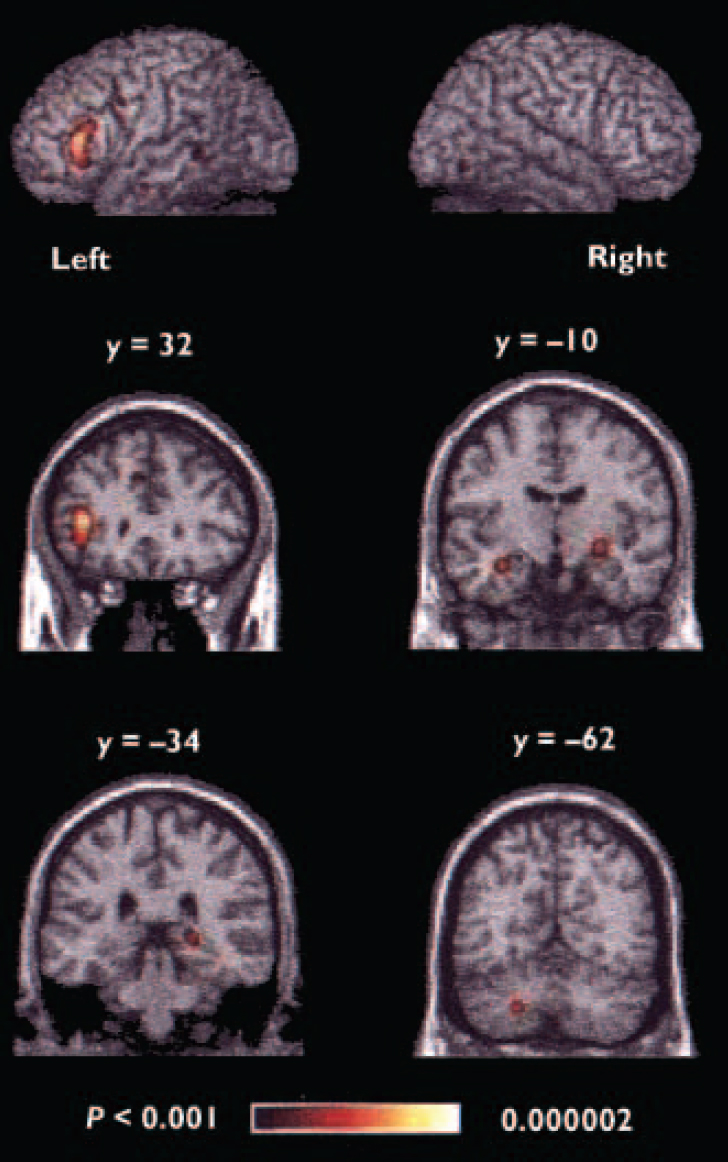

When all foci were included in the meta-analysis, the areas of significant agglomeration were located in the left inferior prefrontal cortex, bilateral medial frontal cortex, anterior cingulate, left precentral/middle frontal gyrus, bilateral anterior medial temporal lobe, right posterior hippocampus, left superior temporal gyrus, bilateral fusiform gyrus and left cerebellum (Table 3, Fig. 1).

Fig. 1 Regions of significant agglomeration of foci in the overall meta-analysis. The y values given for the coronal slices denote the coordinates in the Talairach/MNI system; the colour range represents the above threshold voxel probability.